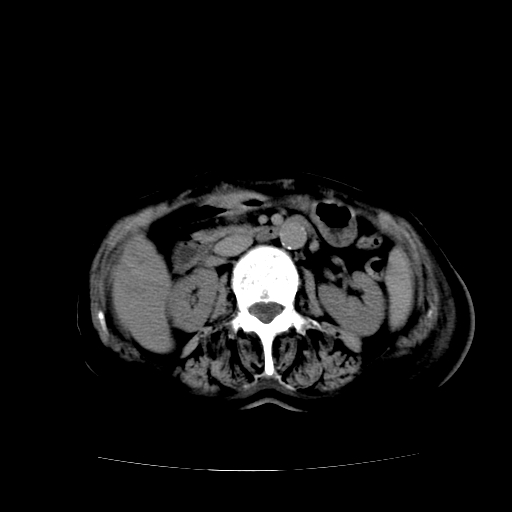

标题: CT17152:女70Y乳腺CA

女70y乳腺ca(针吸活检)

多部位转移瘤的诊断可以肯定,我的疑问是:双肺对称高密度影及胸水是否为心衰肺水肿,病人体虚弱,不好意思图象传的乱![em9]

1)左侧乳腺癌并左侧腋窝及纵隔淋巴结转移,两肺淋巴道转移(癌性淋巴管炎),肝脏多发性转移。2)双侧胸腔积液。3)慢性胆囊炎。

5、肝转移瘤;

6、瓷胆囊。

1)左侧乳腺癌并左侧腋窝及纵隔淋巴结转移,肝脏多发性转移。2)双侧胸腔积液伴双肺蝶翼样磨玻璃高密度影,双侧肺门血管影增粗(图像不全,肺门层面没纵隔窗),考虑心功能不全所致。3)慢性胆囊炎伴壁钙化。